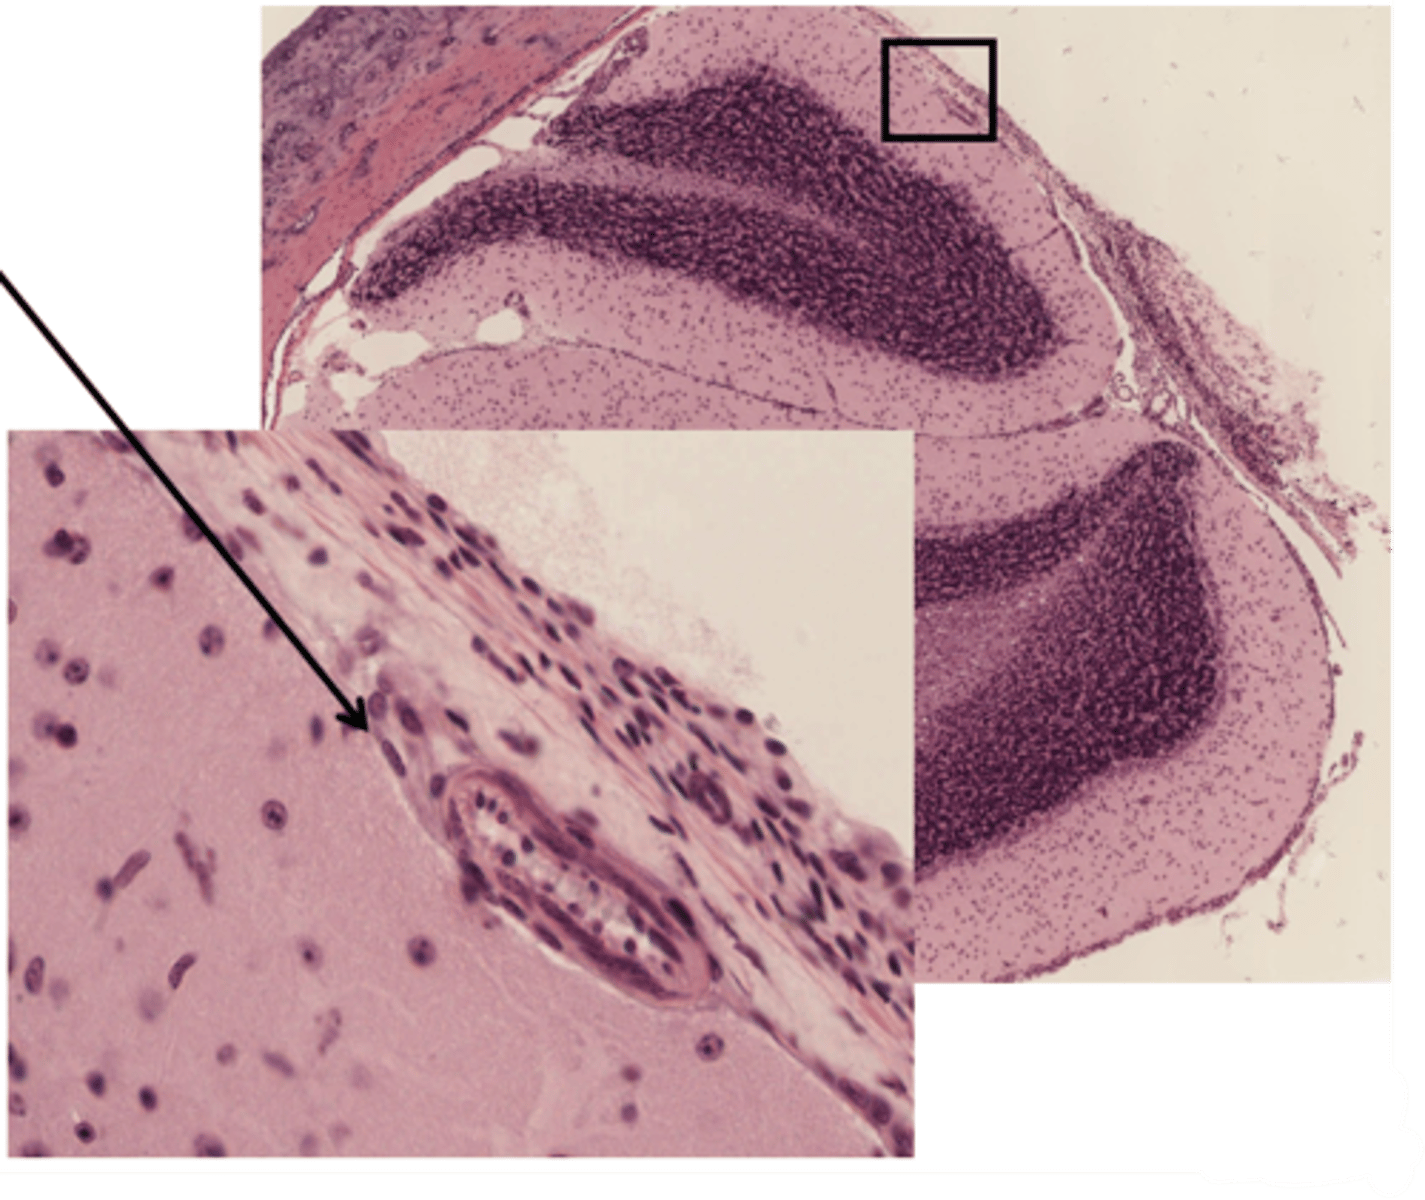

Identify the specific part of the brain in the inset

hippocampus

What part of the hippocampus is at 5 and 6

dentate gyrus

Identify the cells that line the ventricles of the brain and the central canal of the spinal cord

ependymal cells

Identify the part of the meninges

pia mater

arachnoid

dura mater